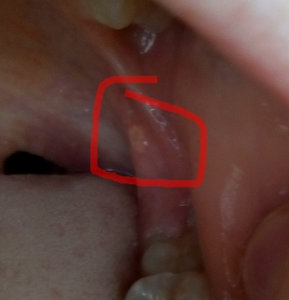

Здравствуйте! Уже год беспокоит какое-то новообразование на верхней десне, внешне она не заметна, но на ощупь примерно как горошина. При нажатии на нее больно, периодически побаливает зуб. У этого зуба удален нерв примерно лет 7-8 назад. Что это может быть? Спасибо.

Добрый день. Это воспаление, так называемый периодонтит. Причина ранее не качественное лечение каналов. Не тяните, обратитесь к врачу , данная проблема может привести к кисте и к потере зуба. Запишитесь к нам на консультацию по многоканальному телефону: (495) 778-47-45. Всего вам доброго!